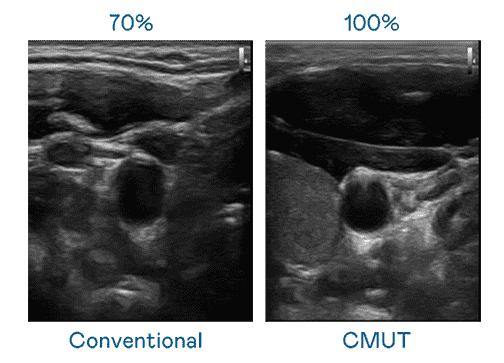

CMUT 技术是一种用电容式微机电元件来产生超音波讯号的技术。。。。与传统 PZT 压电式技术相比,,,CMUT 频宽增加 30%,,,更宽频的超音波讯号让影像解析度大幅提升,,,是实现高影像品质医疗超音波扫描、、促进精准医疗发展的关键技术。。。

大频宽带来超清晰影像

超音波影像的解析度高低,,,首先取决于探头能发出的讯号频宽。。龙门国际 CMUT 可提供高清晰的超音波讯号,,,提供高频宽、、、高灵敏度、、、影像纹理细节更高的超音波影像,,,协助医护人员缩短影像判读时间及利用精准的医疗影像进行诊断。。